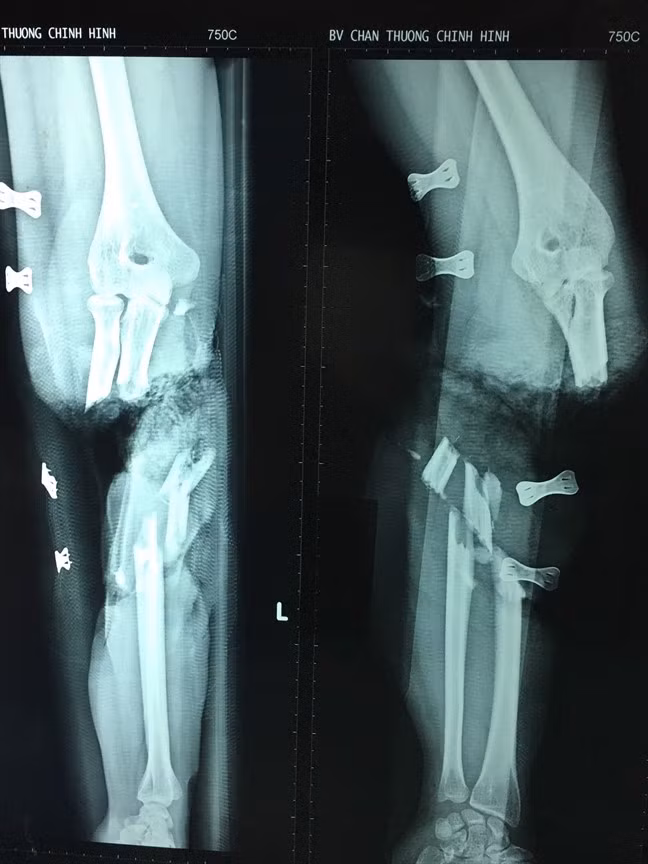

| Hình ảnh X-quang cho thấy cánh tạy bị đứt lìa và có nhiều mảnh xương vụn. |

Hình chụp X-quang cho thấy cánh tay khi bị gãy đã vỡ ra thành nhiều mảnh xương nhỏ. Máy cắt giấy đã cắt cánh tay của nạn nhân đến 2 lần khiến một vị trí gần chỗ đứt đôi bị dập nát.